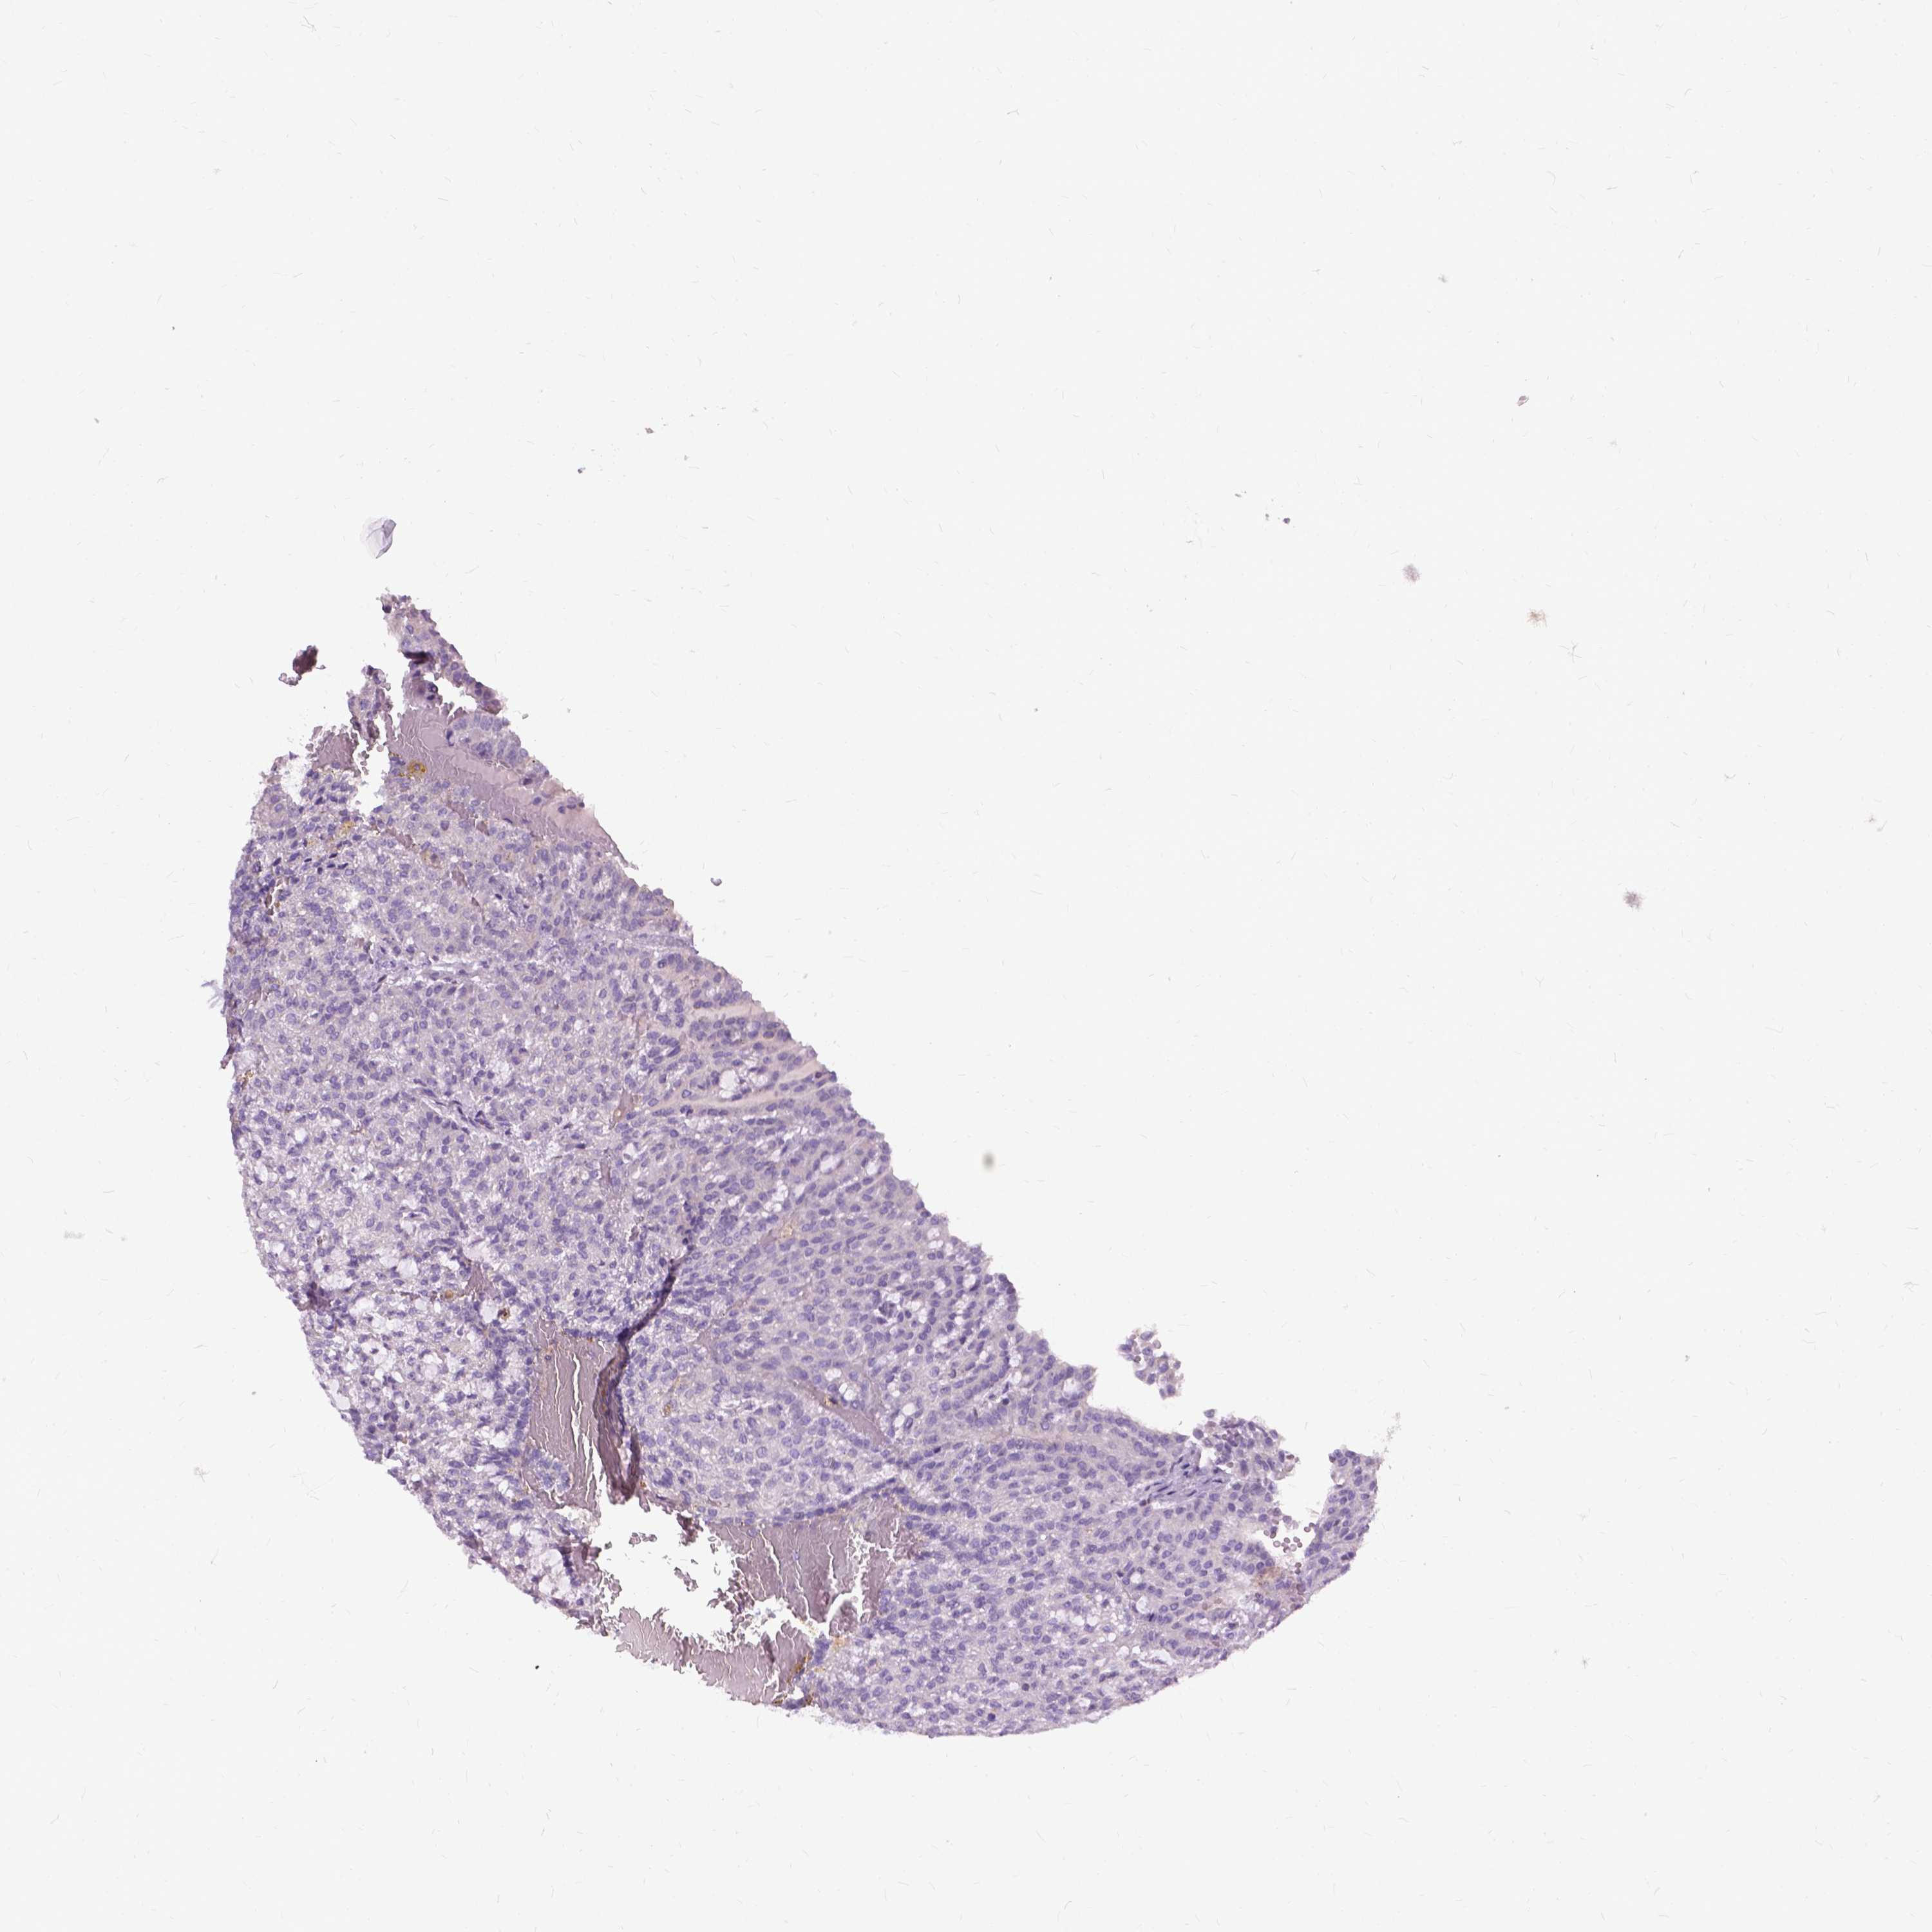

KIDNEY RENAL PAPILLARY CELL CARCINOMA (TCGA) - Interactive survival scatter ploti

The Survival Scatter plot shows the clinical status (i.e. dead or alive) for all individuals in the patient cohort, based on the same data that underlies the corresponding Kaplan-Meier plots. Patients that are alive at last time for follow-up are shown in blue and patients who have died during the study are shown in red.

The x-axis shows the expression levels (FPKM) of the investigated gene in the tumor tissue at the time of diagnosis. The y-axis shows the follow-up time after diagnosis (years). Both axes are complimented with kernel density curves demonstrating the data density over the axes. The top density plot shows the expression levels (FPKM) distribution among dead (red) and alive patients (blue). The right density plot shows the data density of the survived years of dead patients with high and low expression levels respectively, stratified using the cutoff indicated by the vertical dashed line through the Survival Scatter plot. This cutoff is automatically defined based on the FPKM cutoff that minimizes the p-score. The cutoff can be changed by dragging the vertical line or by entering a cutoff value in the square labeled "Current cut-off".

Under the Survival Scatter plot the p-score landscape (black curve; left axis) is shown together with dead median separation (red curve; right axis). Dead median separation is the difference in median mRNA expression between patients who have died with high and low expression, respectively. It is calculated as follows: median FPKM expression of dead patients with high expression - median FPKM expression of dead patients with low expression. This is intended to aid the user in visually exploring custom cutoffs and the associated p-scores and dead median separation.

Individual patient data is displayed and can be filtered by clicking on one or more of the category buttons on the top of the page. Categories describing expression level and patient information include: high, low, alive, dead, female, male and tumor stages. The scale of the x-axis can be toggled between linear and log-scale by clicking on the "x log" button. Mouse-over function shows TCGA ID, patient information and mRNA expression (FPKM) for each patient.

& Survival analysisi

Kaplan-Meier plots summarize results from analysis of correlation between mRNA expression level and patient survival. Patients were divided based on level of expression into one of the two groups "low" (under cut off) or "high" (over cut off). X-axis shows time for survival (years) and y-axis shows the probability of survival, where 1.0 corresponds to 100 percent.

JAK3 is not prognostic in Kidney Renal Papillary Cell Carcinoma (TCGA)

Best expression cut offi

Based on the FPKM value of each gene, patients were classified into two groups and association between prognosis (survival) and gene expression (FPKM) was examined. The best expression cut-off refers the FPKM value that yields maximal difference with regard to survival between the two groups at the lowest log-rank P-value. Best expression cut-off was selected based on survival analysis .